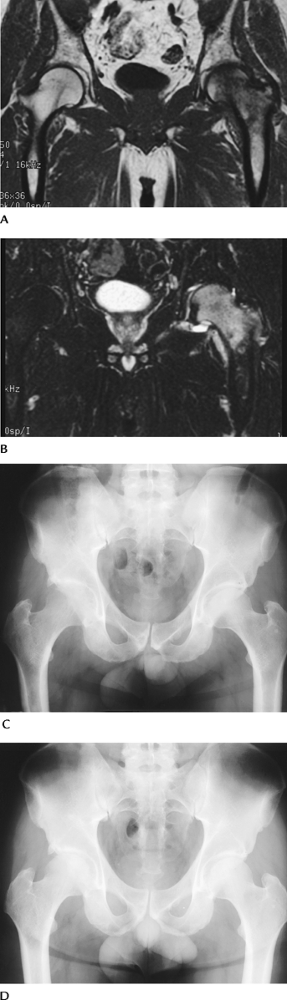

FIGURE 4-36 Coronal T1- (A) and T2- (B)

weighted images demonstrate abnormal signal intensity in the left femoral head and neck in a patient with hip pain. Radiographs in a different patient showing osteopenia in the right hip during the symptomatic phase (C) and return to normal (D) 6 months later. |